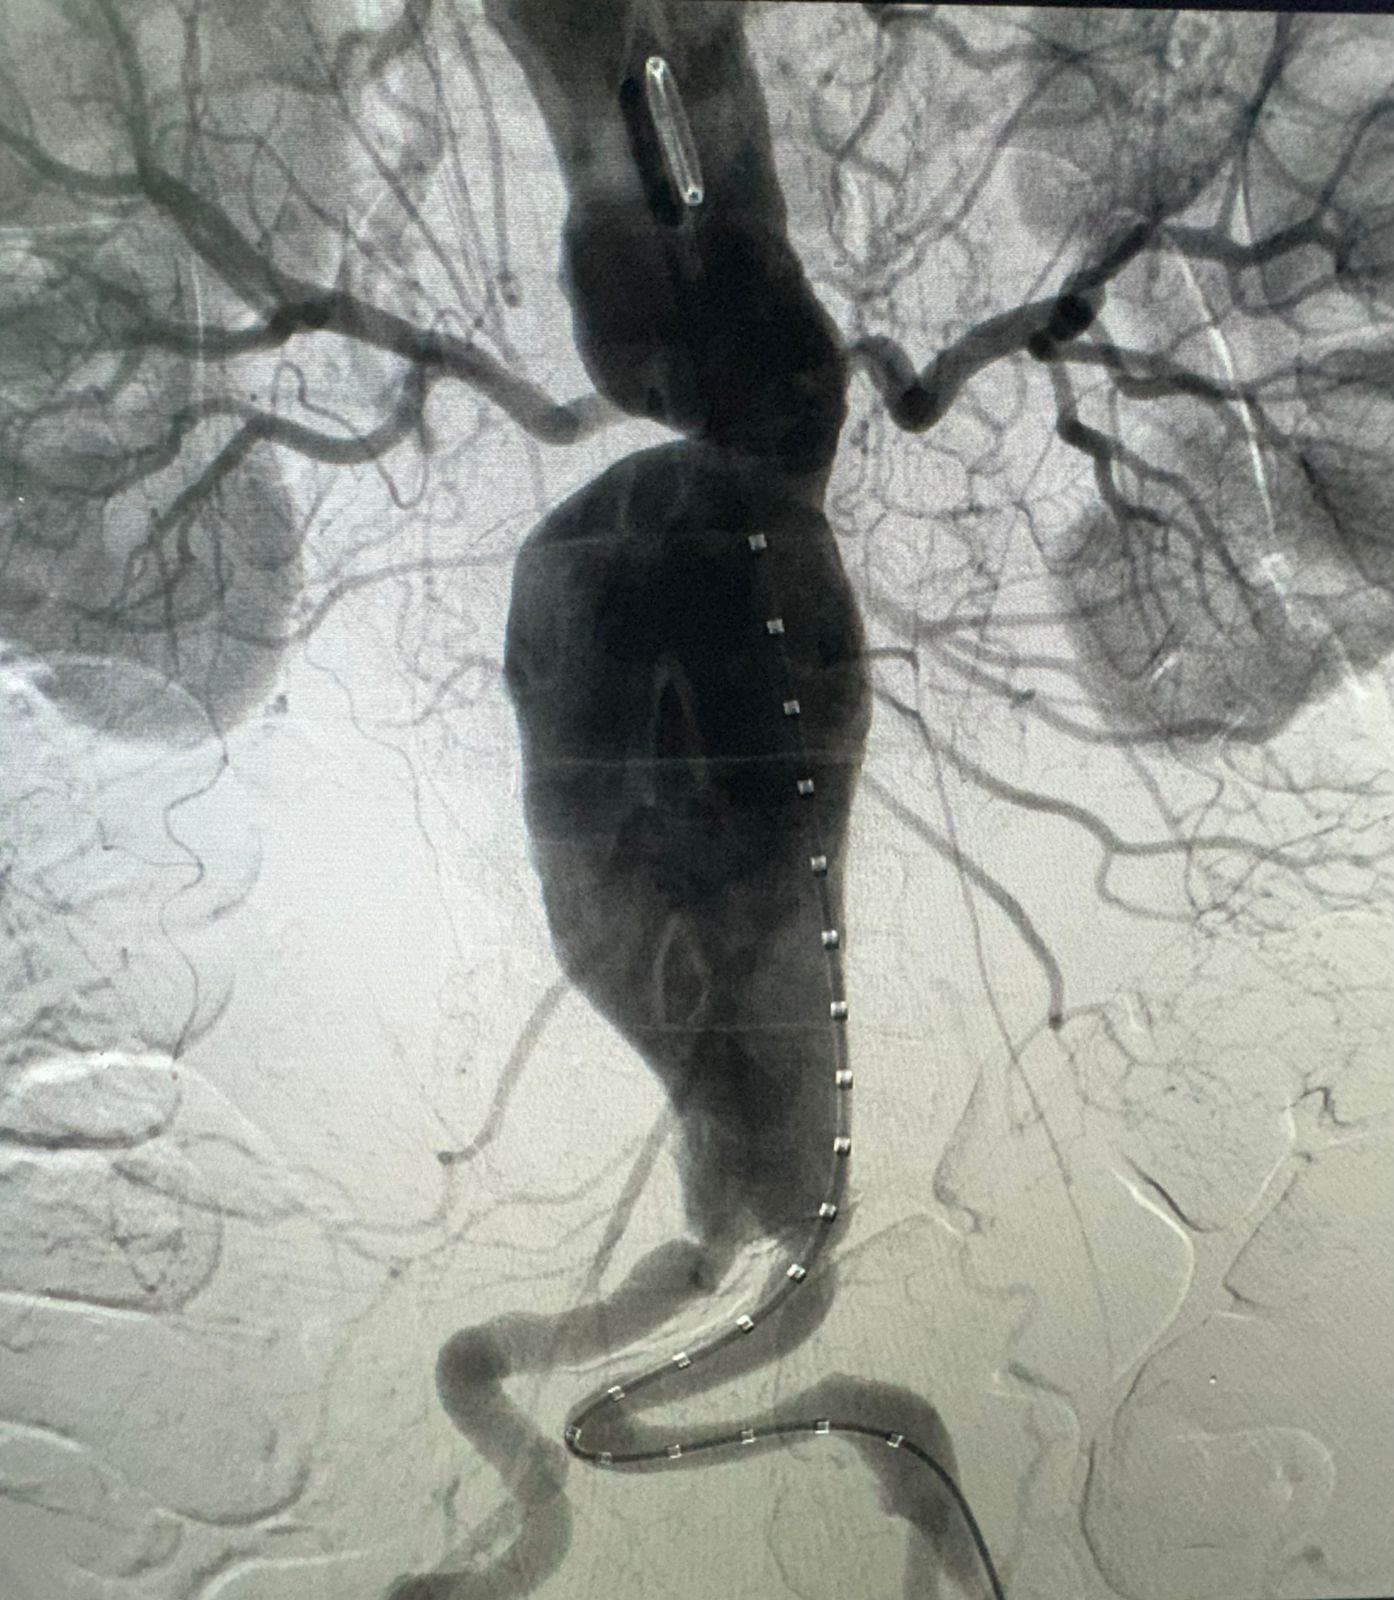

Un grupo de cirujanos, encabezado por Andrés Marín, pasado presidente de la Sociedad Dominicana de Cirugía Vascular y Endovascular, realizó el primer procedimiento Fevar en el país, que consiste en tratar un aneurisma aórtico abdominal complejo de cuello muy corto.

La técnica de reparación aórtica endovascular por fenestración (Fevar, por sus siglas en inglés) consiste en revascularizar las arterias mediante fenestras (orificios donde coinciden las arterias renales) e implantes de stents revestidos adicionales.

El galeno aclaró que ya es frecuente en el país reparar los aneurismas aórticos no complejos mediante la técnica de reparación endovascular (Evar), sin embargo, ésta fue la primera vez que se realizó con implantes de vasos adicionales mediante la fenestración.

“Es un hito. Es un procedimiento enormemente técnico. Uno entra por catéteres dentro de la arteria y repara todo llevando todas las piezas chiquitas por dentro de esa arteria”, dijo.

Para ello, se conformó un equipo de cuatro cirujanos endovasculares, con Marín como médico principal, quienes realizaron el procedimiento a un paciente de 77 años de edad en un récord de 3.5 horas en el Hospital Metropolitano de Santiago (HOMS).